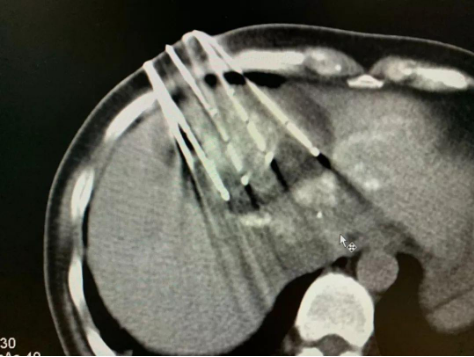

术前检查单

术后复查单